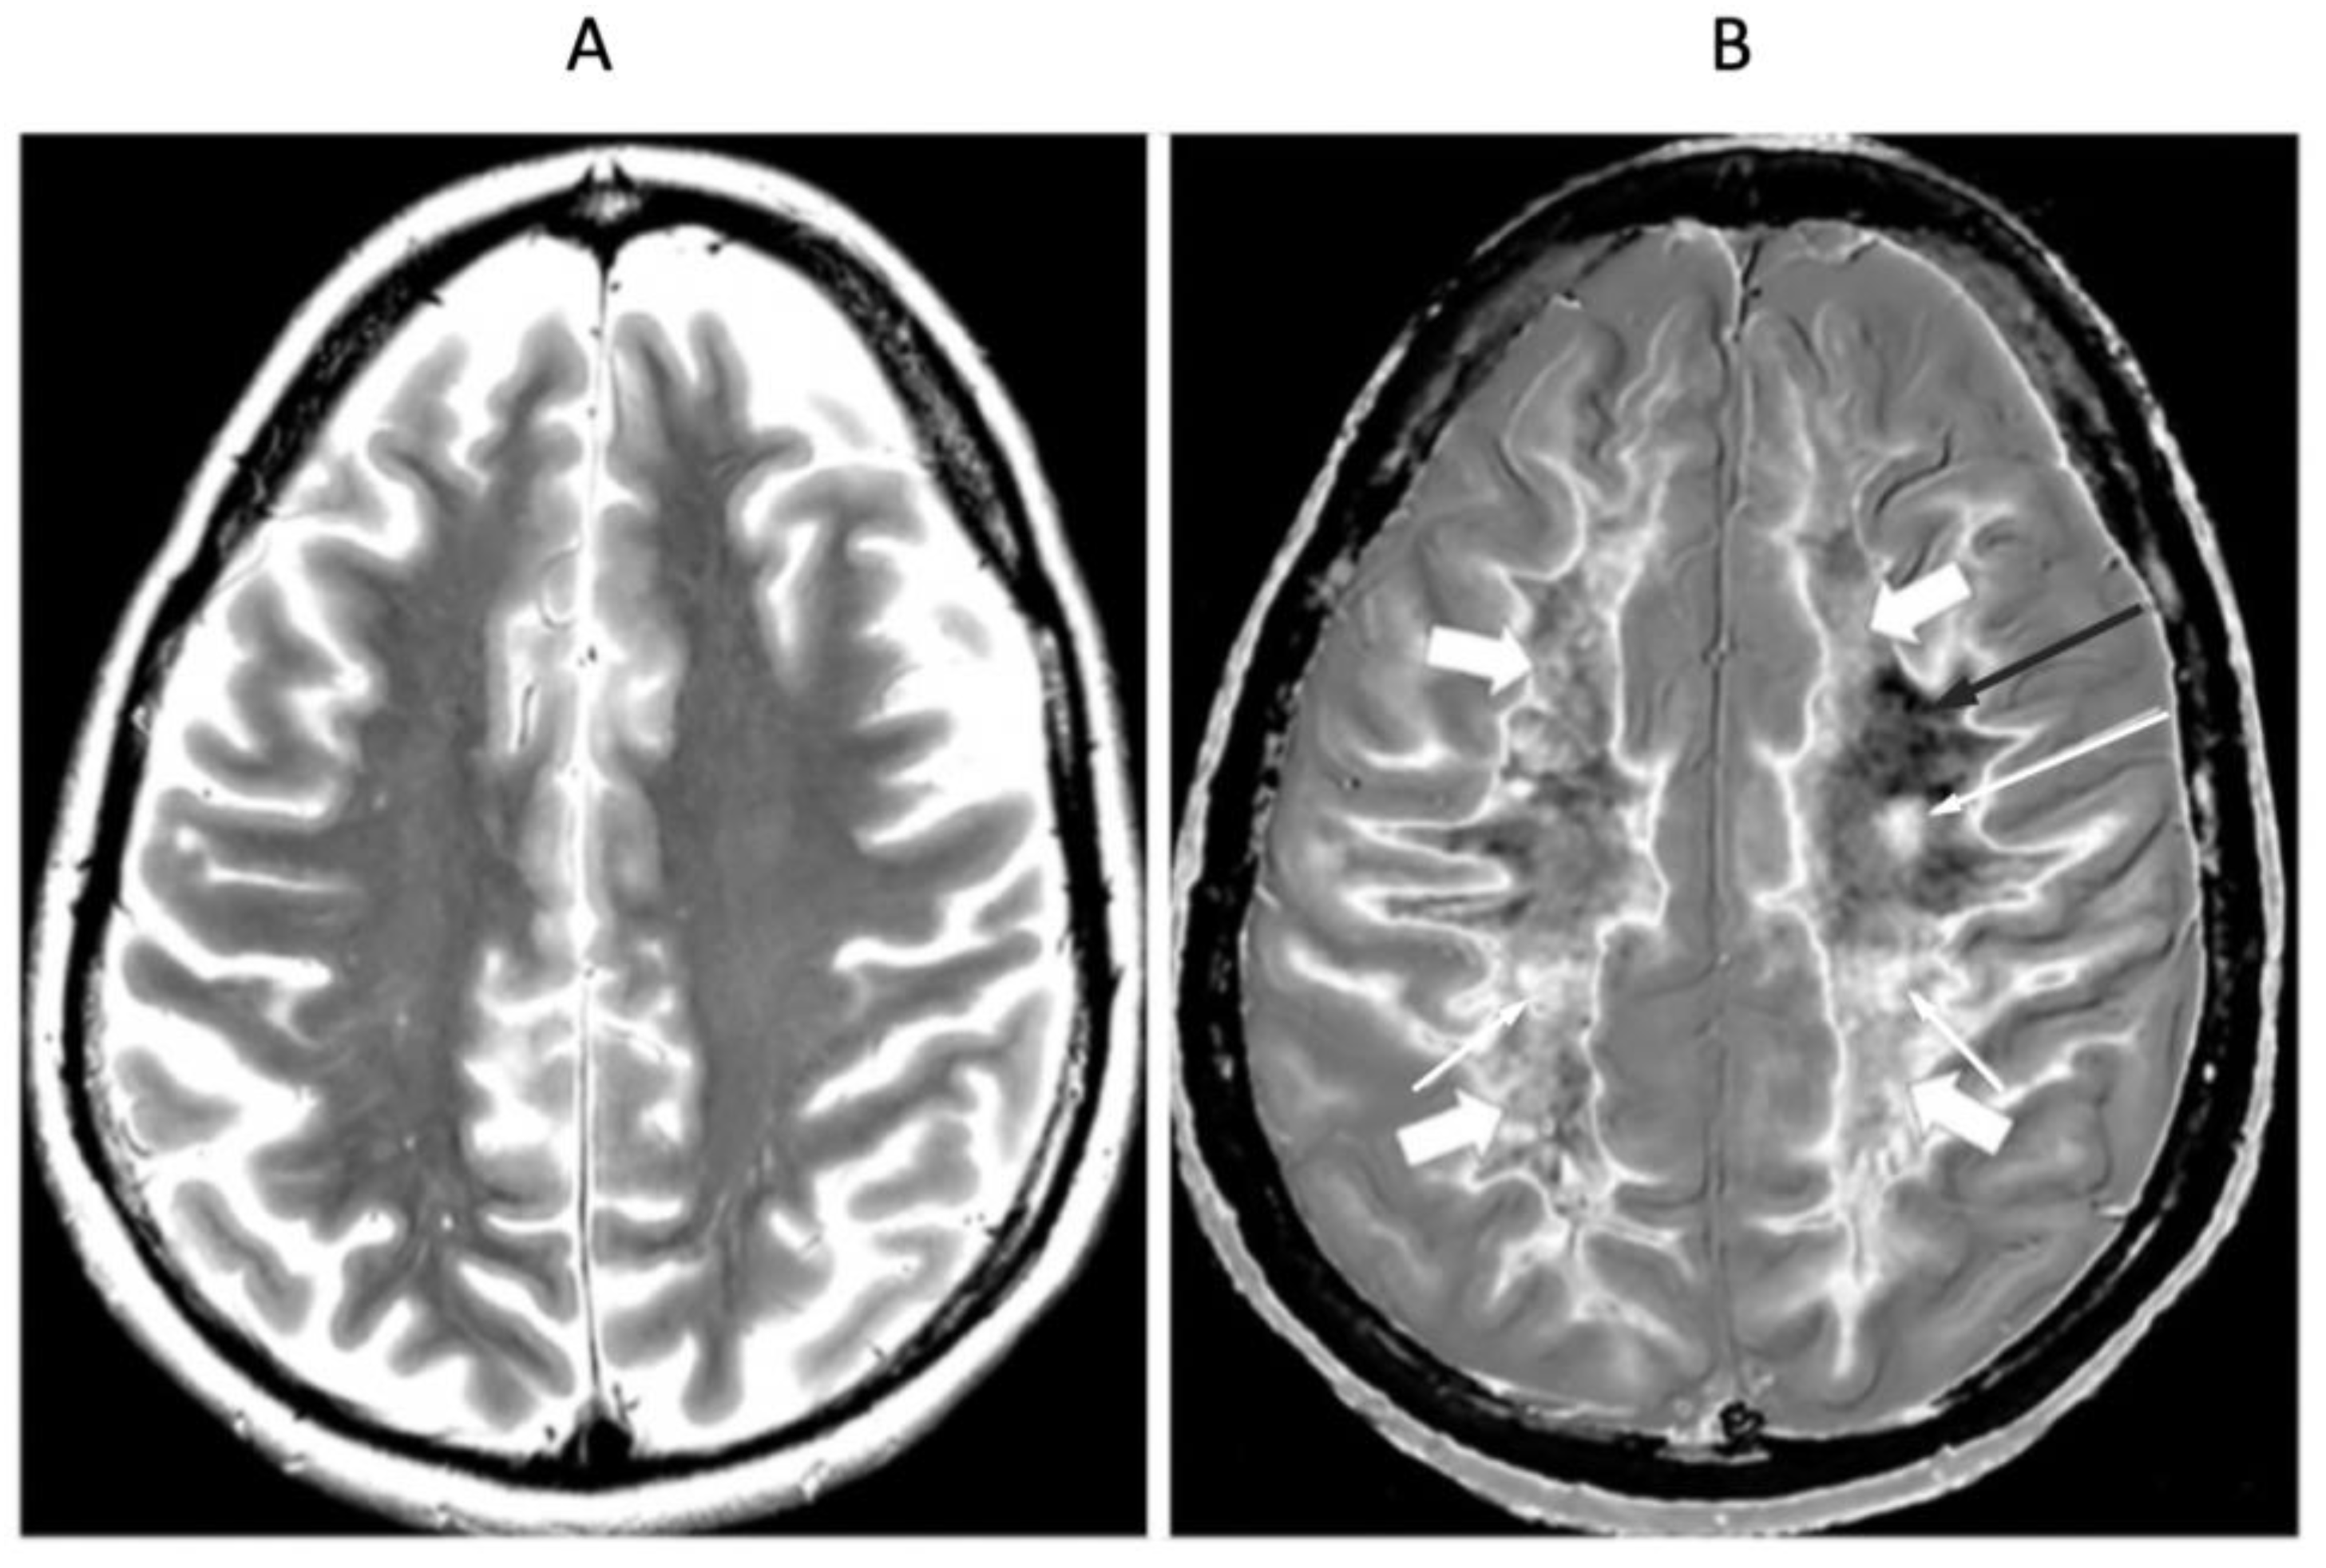

4. Illustrative Cases

5.2.1. Whiteout Sign

5.2.2. Grayout Signs